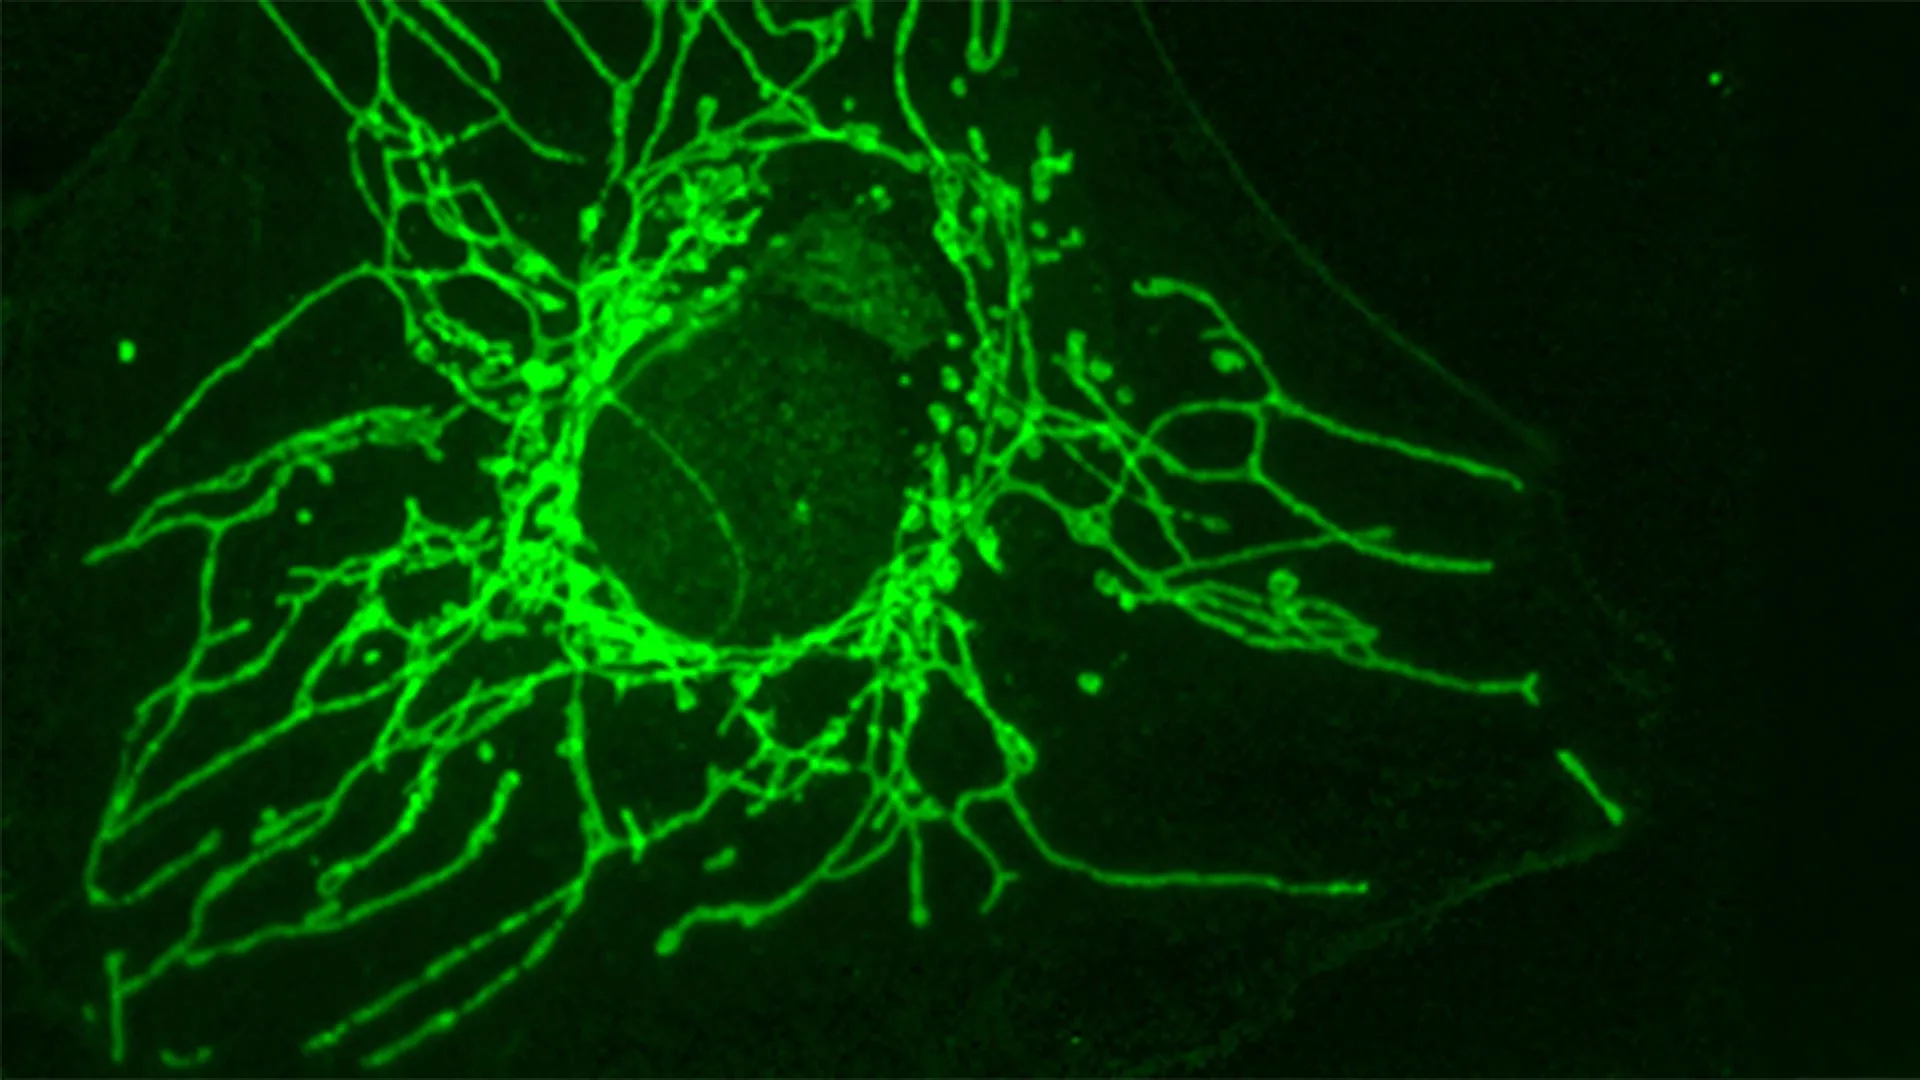

Os pesquisadores, liderados pelo Professor Honorário Jean-Claude Martineau, do Departamento de Biologia Molecular e Celular da Faculdade de Ciências da UNIGE, investigaram como diferentes aminoácidos afetam o crescimento das células cancerígenas. Seus experimentos mostraram que a versão D da cisteína (D-Cys), que contém um átomo de enxofre, pode suprimir fortemente o crescimento de certas células cancerígenas em testes de laboratório. No entanto, as células saudáveis não foram afetadas.

“Esta diferença entre células cancerígenas e células saudáveis é facilmente explicada: o D-Cys é importado para a célula através de um transportador específico que só está presente na superfície de certas células cancerígenas”, explica Josephine Zangari, estudante de doutoramento no laboratório do Prof. “Na verdade, observámos que se expressássemos este transportador na superfície de células saudáveis, essas células paravam de proliferar na presença de D-Cys”.

Trabalhando com o professor Roland Lill da Universidade de Marburg e sua equipe, os pesquisadores descobriram como o D-Cys danifica as células cancerígenas.

“Ela bloqueia uma enzima essencial chamada NFS1, que está localizada nas mitocôndrias – a ‘casa de força’ da célula. Esta enzima desempenha um papel importante na formação de aglomerados de ferro-enxofre, pequenas estruturas que são essenciais para muitos processos, como respiração celular, produção de DNA e RNA e manutenção genética de Roland.

Quando o NFS1 é bloqueado, várias funções celulares importantes são interrompidas. A respiração das células cancerosas fica mais lenta, os danos ao DNA aumentam e o ciclo celular para. Juntos, esses efeitos impedem que as células continuem a crescer e a se dividir.